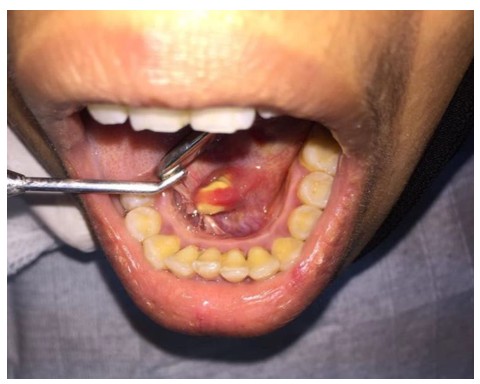

We present a case of a 17-year-old female patient with complaint of a recurrent painful swelling in anterior floor of mouth region which was present for over 3 years. On intraoral examination, a hard, mobile and slightly tender nodule was palpable in the left Wharton’s duct opening area (Fig. 1). A lower occlusal radiograph showed a radiopaque mass with defined limits in the left anterior half of the floor of the mouth consistent with the diagnosis of sialolith (Fig. 2).

The extraction of the sialolith was done under local anesthesia via an incision directly over the stone (Fig. 3 and 4). The sialolith was measuring approximately about 17 × 10 mm in size and was brownish in color (Fig. 5). Following removal of sialolith the incision was closed and the patency of the duct orifice was confirmed (Fig. 6).